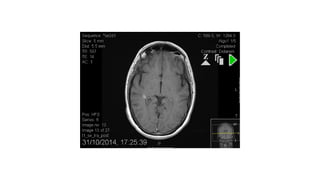

T1 lesions with gadolinium enhancement

T1 ‘BLACKHOLES’ HYPOINTENSE LESIONS